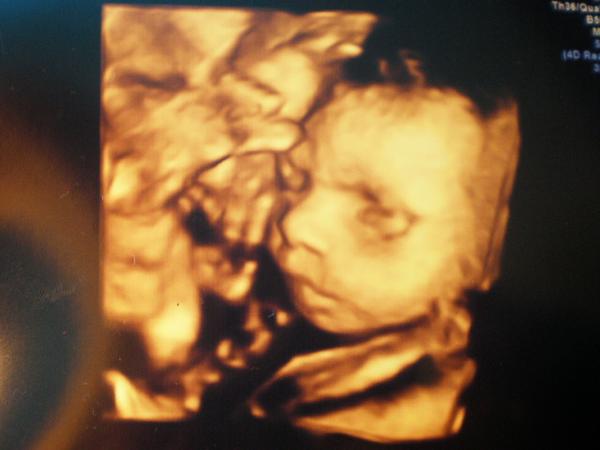

@maximka33 @eva518 @matysikovad @ofina1 ahojte holky, tak pak doktor řekl, že malej je v pořádku. Váží necelý kilo. Nechtěl se nám moc ukázat, šmudlal si ručičkou pusinku a nosánek, pak byl otočenej k placentě. Nejlepší bylo, když zíval 😀 to bylo nádherný. Pořád mlel pusinkou a doktor řekl, že je ukecanej a že to má asi po mě 😀 tady máte fotečku 😉 děkuju za podporu všem 🙂 Jen nevím po kom má ten palec na noze 😀